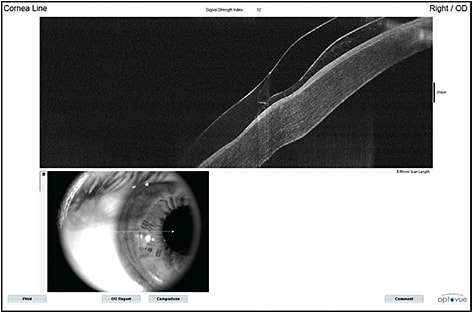

Figure 1a. Use of optical coherence tomography (OCT) to show the junction profile of an older-generation Synergeyes KC lens on a keratoconic eye. Note the basic design of the transition between the GP and hydrogel soft lens portions.

Figure 1b. Junction profile of the newest-generation UltraHealth lens on a keratoconic eye. Note the reverse geometry inner landing zone transitioning to a broader, cushioning SiHy soft skirt.